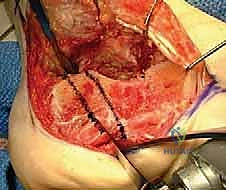

- إزالة النتوءات العظمية الضاغطة (Exostectomy):

يقوم الدكتور هطيف بإزالة الكتلة العظمية الزائدة التي تبرز من الجانب الخارجي للكعب. هذه الخطوة ضرورية جداً لتحرير الأوتار الشظوية (Peroneal Tendons) وتخفيف الضغط عن عظم الشظية، مما يقضي على الألم الجانبي ويسهل ارتداء الأحذية.

- القطع العظمي التصحيحي (Corrective Osteotomy):

إذا كان الكعب قد فقد ارتفاعه أو انحرف بشكل كبير، يقوم الدكتور هطيف بإجراء قطع دقيق في عظم الكعب لإعادة توجيهه إلى محوره الميكانيكي السليم. يتم استخدام طعوم عظمية (Bone Grafts)—تؤخذ غالباً من حوض المريض أو طعوم صناعية—لرفع الكعب المنهار واستعادة زاوية بوهلر الطبيعية.

- إعادة بناء الأوتار والأربطة:

في حالة تضرر الأوتار الشظوية بسبب الانحشار الطويل، يتم تنظيفها وإصلاحها وإعادة توجيهها في مسارها السليم لضمان استعادة القوة العضلية للقدم.